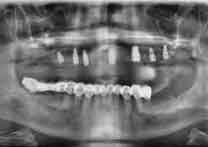

(22)

Before Treatment

OPG (Pre Treatment)

After Areatment

OPG (Post Treatment)

Case of full mouth rehabilitation All teeth extracted Upper single complete denture and lower Implant supported denture